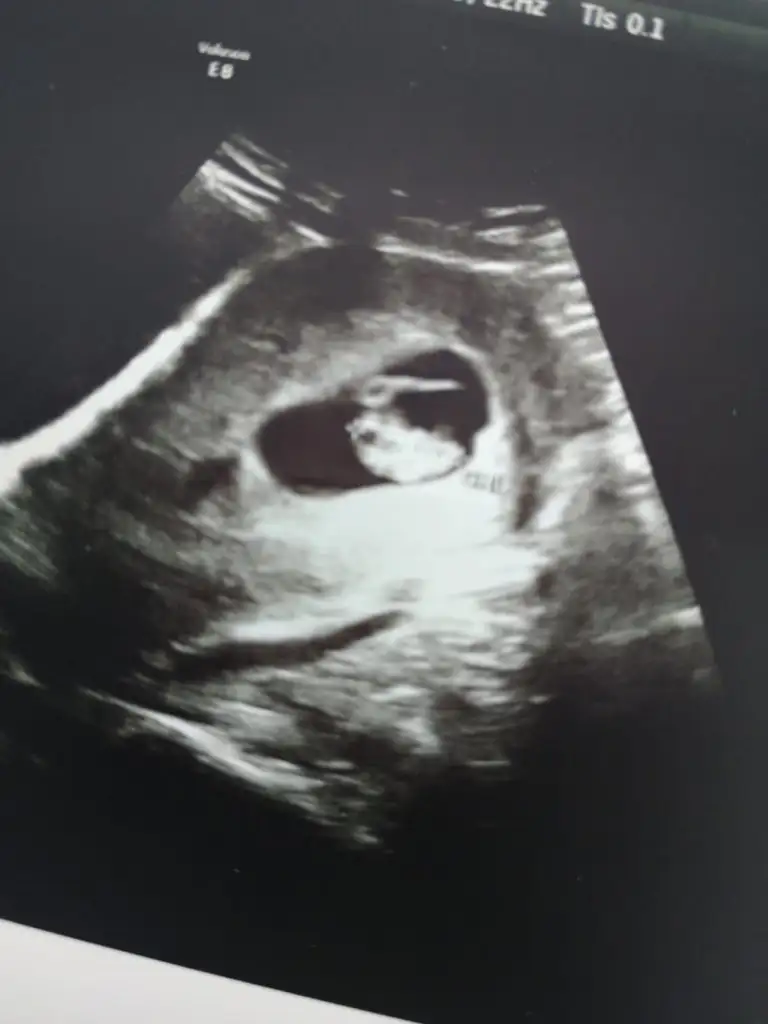

Merhaba 7 buçuk haftalık tahmin ederseniz sevinirim☺️

• IMG-20220628-WA0005.webp

IMG-20220628-WA0005.webp

21,7 KB · Görüntüleme: 67

• IMG-20220628-WA0006.webp

IMG-20220628-WA0006.webp

18,8 KB · Görüntüleme: 74